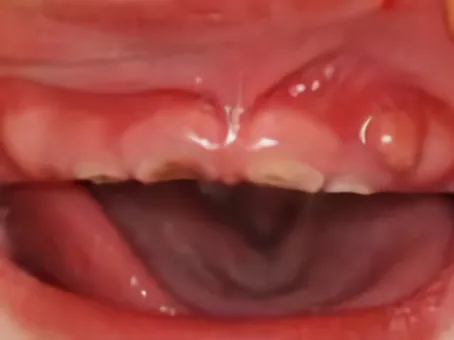

子供の虫歯

乳歯はその後に出てくる永久歯より小さく、特に歯のエナメル質、象牙質とも永久歯と比較して遙かに薄く、歯の質も軟らかく、虫歯になりやすい構造です。

また、歯の神経が入っている部屋(歯髄腔)は永久歯のそれより比較的大きく、形は角が出たように突起しています。そのためお子さんの虫歯は多発しやすく、進行が早いので、

注意が必要なのです。しかしその反面、フッ素の取り込みが良く、虫歯予防効果を出しやすい利点もあります。